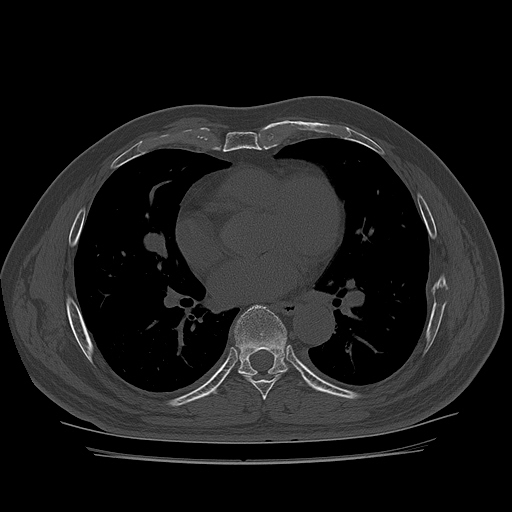

CT ; metastacic mass at rib and adjacent lung

CT image

1893637843_a950dd50_CT162942146.jpg

1893637843_088e702a_CT162942147.jpg